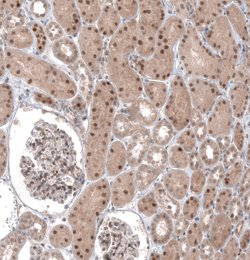

The basic helix-loop-helix transcription factor TCF21/Pod1 (also called capsulin or epicardin) is involved in kidney, lung and spleen organogenesis. It is also essential for normal development of the testes and ovaries. TCF21/Pod1 is involved in the transcriptional repression of steroidogenic factor 1 (Sf1/Nr5a1/Ad4BP), an orphan nuclear receptor that regulates the expression of multiple genes (including Scc) that mediate sexual differentiation.

| Immunohistochemistry, Western Blot | |